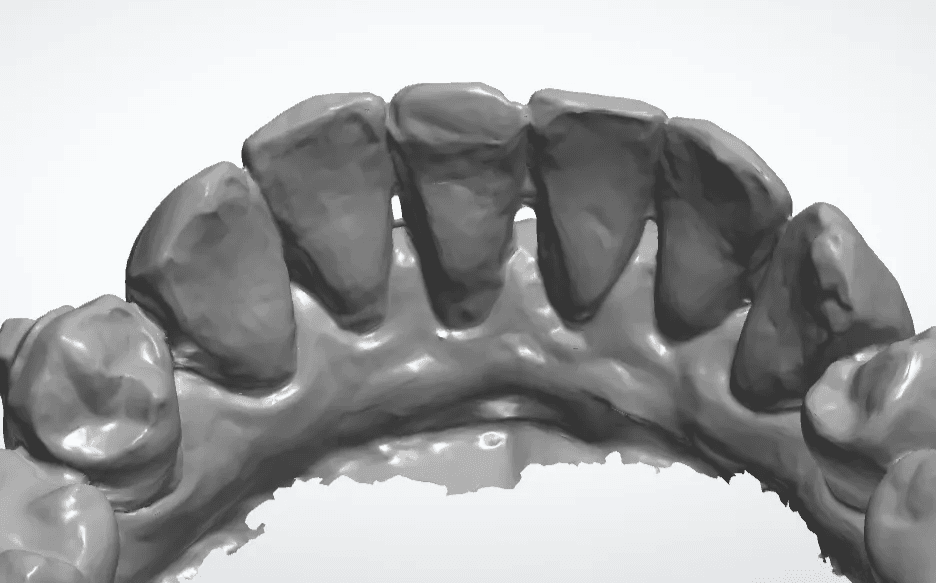

Escaneamento sem contenção

Escaneamento com contenção removida virtualmente

Quanto maior a precisão da cópia do nosso escaner maior será a acurácia da movimentação planejada.